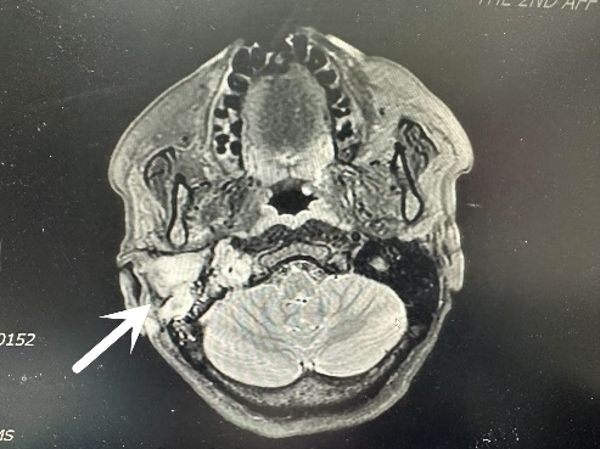

患者因咳嗽入住我院呼吸与危重症医学科,医生完善颅脑CT时发现肿瘤,请耳鼻咽喉头颈外科病院会诊后转入吴宝俊、李阳教授组。患者在耳鼻咽喉头颈外科病院进行进一步的检查,吴宝俊对肿瘤组织取活检病理,同时邀请相关科室会诊,最终各种检查及病理结果提示病人多发副神经节瘤:颈静脉球瘤+双侧颈动脉体瘤+中耳胆脂瘤。肿瘤较大且供血丰富,且包绕颈总动脉、颈外动脉,同时侵犯颅底岩骨段的颈内动脉,与后组颅神经关系密切,手术难度极大。

“副神经瘤多发更是极为罕见,即使在驰名世界的意大利皮亚琴察Gruppo Otologico 颅底中心,一年的手术也仅10例左右,在西北地区更是没有开展此类手术的先例。”西安交通大学第二附属医院耳鼻咽喉头颈外科病院主任任晓勇谈到,此类手术涉及颅底、颈部大血管,手术难度及风险极高,科室即刻进行重大疑难病例讨论(MDT),请相关科室及专家讨论手术实施方案及手术风险预防及处理措施。经会诊讨论后,决定行一期同侧颈静脉球切除术+颈动脉体瘤切除术+面神经-舌下神经吻合术。同时,医生做了充分的手术预案,如出现颈内动脉或其他大血管的损伤,则行覆膜支架。

手术中,耳科组教授吴宝俊、李阳主刀先行切除颈动脉体瘤,再行颈静脉球切除术+面神经-舌下神经吻合术,手术持续10余小时,在保留颈内动脉的基础上完整切除肿瘤,并保留后组颅神经功能。头颈组教授梁建民、盛颖协助,麻醉科李伟、薛丽教授保驾护航,手术室刘雄涛、李荣、邓睿、王旭斌等配合作。